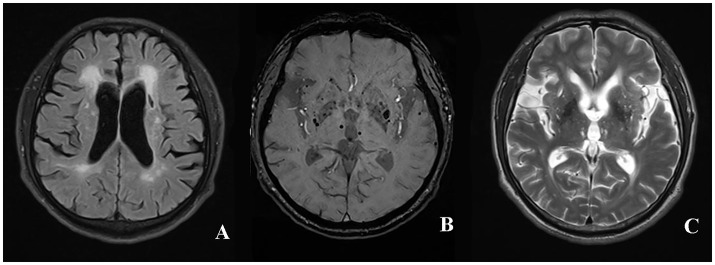

Fazekas grades. Мультифокальная лейкоэнцефалопатия. Резидуальная энцефалопатия на мрт. Прогрессирующая мультифокальная лейкоэнцефалопатия кт. Гипертензионная энцефалопатия на мрт.

Fazekas grades. Мультифокальная лейкоэнцефалопатия. Резидуальная энцефалопатия на мрт. Прогрессирующая мультифокальная лейкоэнцефалопатия кт. Гипертензионная энцефалопатия на мрт.

Fazekas grades. Инсульт на Dwi. Лейкоареоз Фазекас. Инсульт Dwi Flair несоответствие. Brain stroke MRI.

Fazekas grades. Инсульт на Dwi. Лейкоареоз Фазекас. Инсульт Dwi Flair несоответствие. Brain stroke MRI.